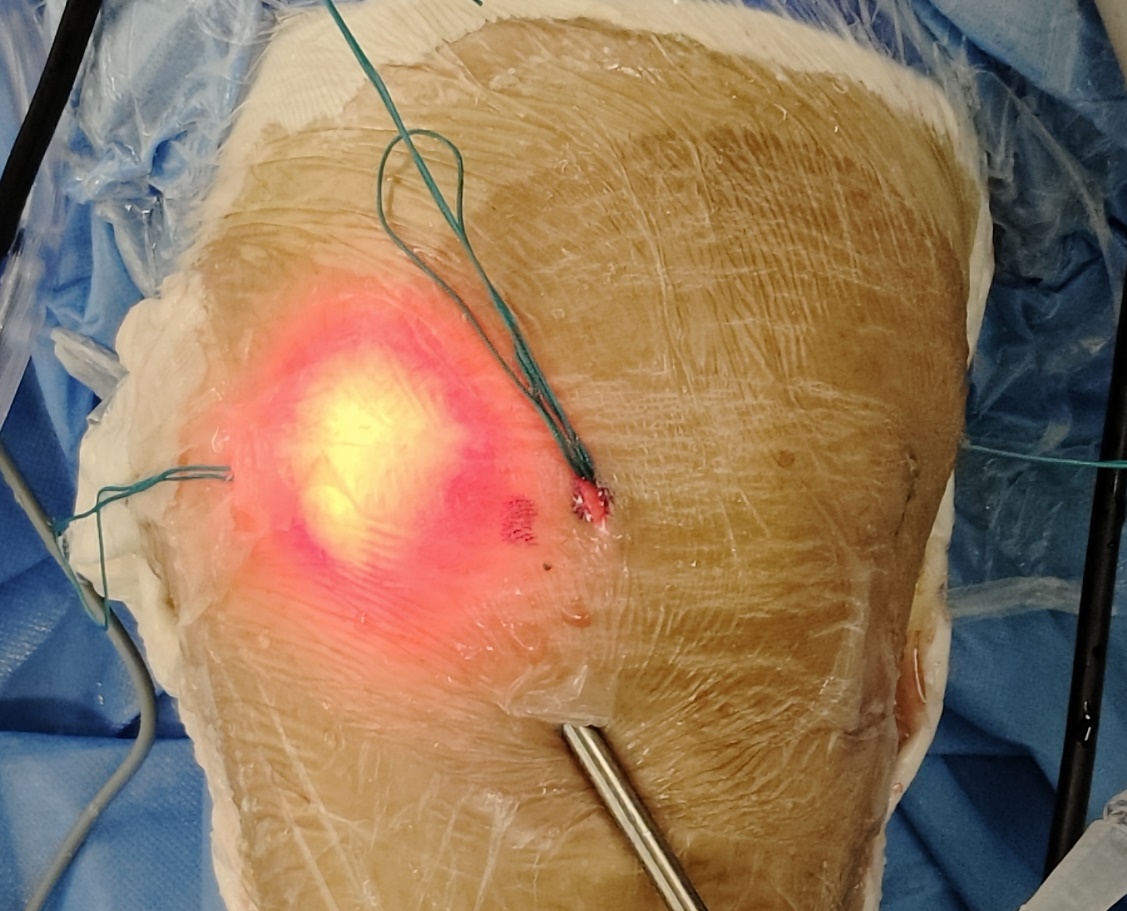

三、术后伤口表现

传统微创关节镜辅助术式          全镜下微创术式